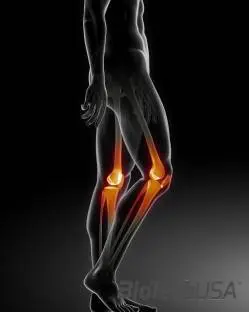

Az ízületi porcsérülések leggyakrabban a térdet érintik. Az ízületi porcok feladata a csontok védelme. Porcsérüléskor arról van szó, hogy az ízületi porcok folyamatos károsodása, terhelése miatt a porcfelszín vékonyodik, emiatt a kapcsolódó csontok egymást, vagy az ízület szélét érik, s ez az érintkezés, dörzsölés gyulladásos állapotot eredményez, mely igen erős fájdalmat okoz.

A porcsérülések leggyakrabban a térdben lévő porcok fizikai terhelés következtében kialakult sérülései, melyek már fiatal korban – különösen az intenzíven sportolók körében – fordulnak elő. Nagyon sok esetben ezek a porcsérülések egy korábbi sérülés következtében alakulnak ki./sites/testbiotechusashop/documents/news/_extra/1449/o_Fotolia_30690612_M_20130620124210.jpg

Ízületi ficam akkor alakul ki, ha a két ízület közötti kapcsolat részlegesen vagy teljesen megszakad, vagyis az ízületi porcfelszínek elmozdulnak egymástól. Az ízületeket erős ízületi tok és szalagok veszik körül. Ficam esetén ennek a toknak a szalagjai szakadnak el részben vagy teljesen. A sportolás közben „kialakult“ ficamok tehát az ízület porcfelszínének sérülését okozzák.

Teljes ficam esetén a két porcfelszín teljesen eltávolodik egymástól, míg a részleges ficamnál  az ízületi felszínek részben még érintik egymást, viszont a csontok helyzete már nem anatómiás. Teljes ficam leggyakrabban a vállízületben, könyök-, ujjízületekben és a térdkaláccsal fordul elő. Részleges ficam a térdben és bokában jön létre leginkább.

Legtöbb esetben azért sérülnek le az emberek sport közben, mert az izmaik túl gyengék, illetve nincs meg az egyensúly az ellentétes izomcsoportok között. Másrészt viszont fokozhtaja a sérülés bekövetkezését a sportot megelőző bemelegítés elhagyása. Leggyakrabban a sérülések a hobbi sportok közben alakulnak ki (mint például: síelés, foci, kosárlabda, kézilabda, squash, aerobik, stb). Az esetek nagy részében ezeknél a sportoknál leginkább a térdízület sérül.